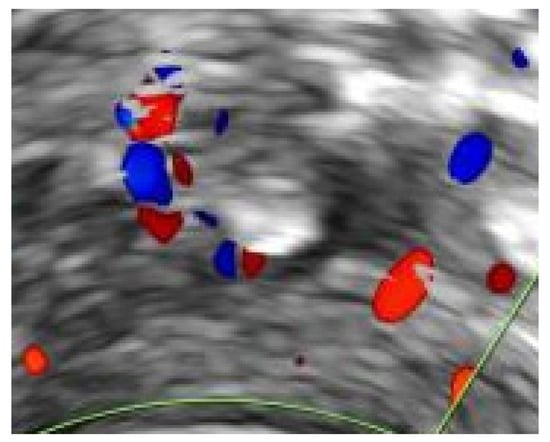

- Mavrelos, D.; Cohen, H.; Pateman, K.; Hoo, W.; Foo, X.; Jurkovic, D. Diagnosis of uterine vein thrombosis on transvaginal ultrasound. Ultrasound Obstet. Gynecol. 2013, 42, 480–483. [Google Scholar] [CrossRef] [Green Version]